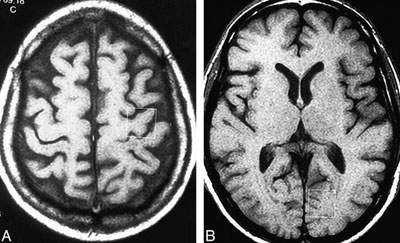

ـ اسکن MRI